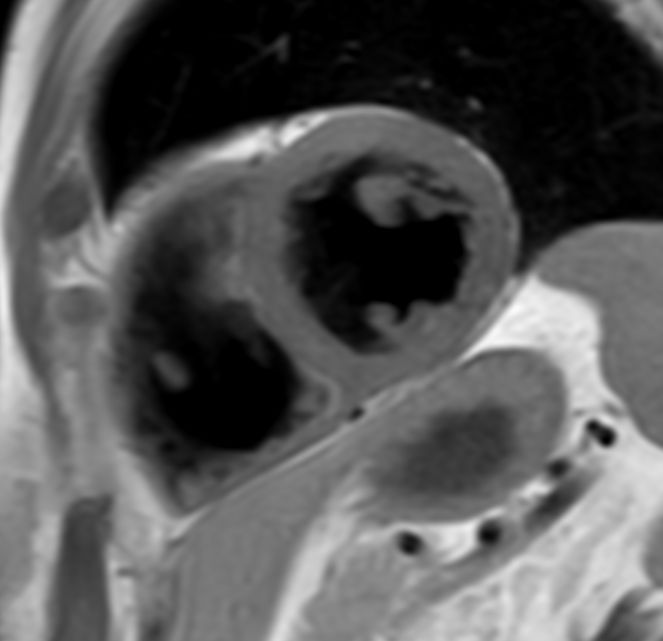

bTFE short axis With Compressed SENSE: 4.8 sec breath hold